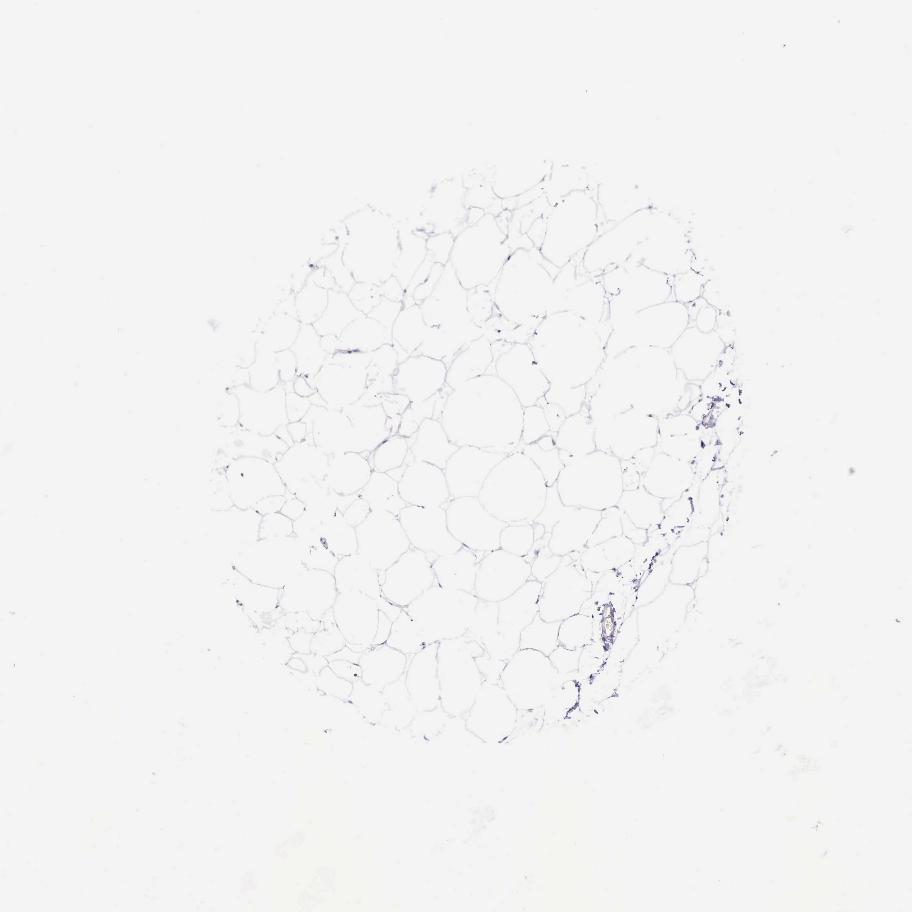

ADIPOSE TISSUE